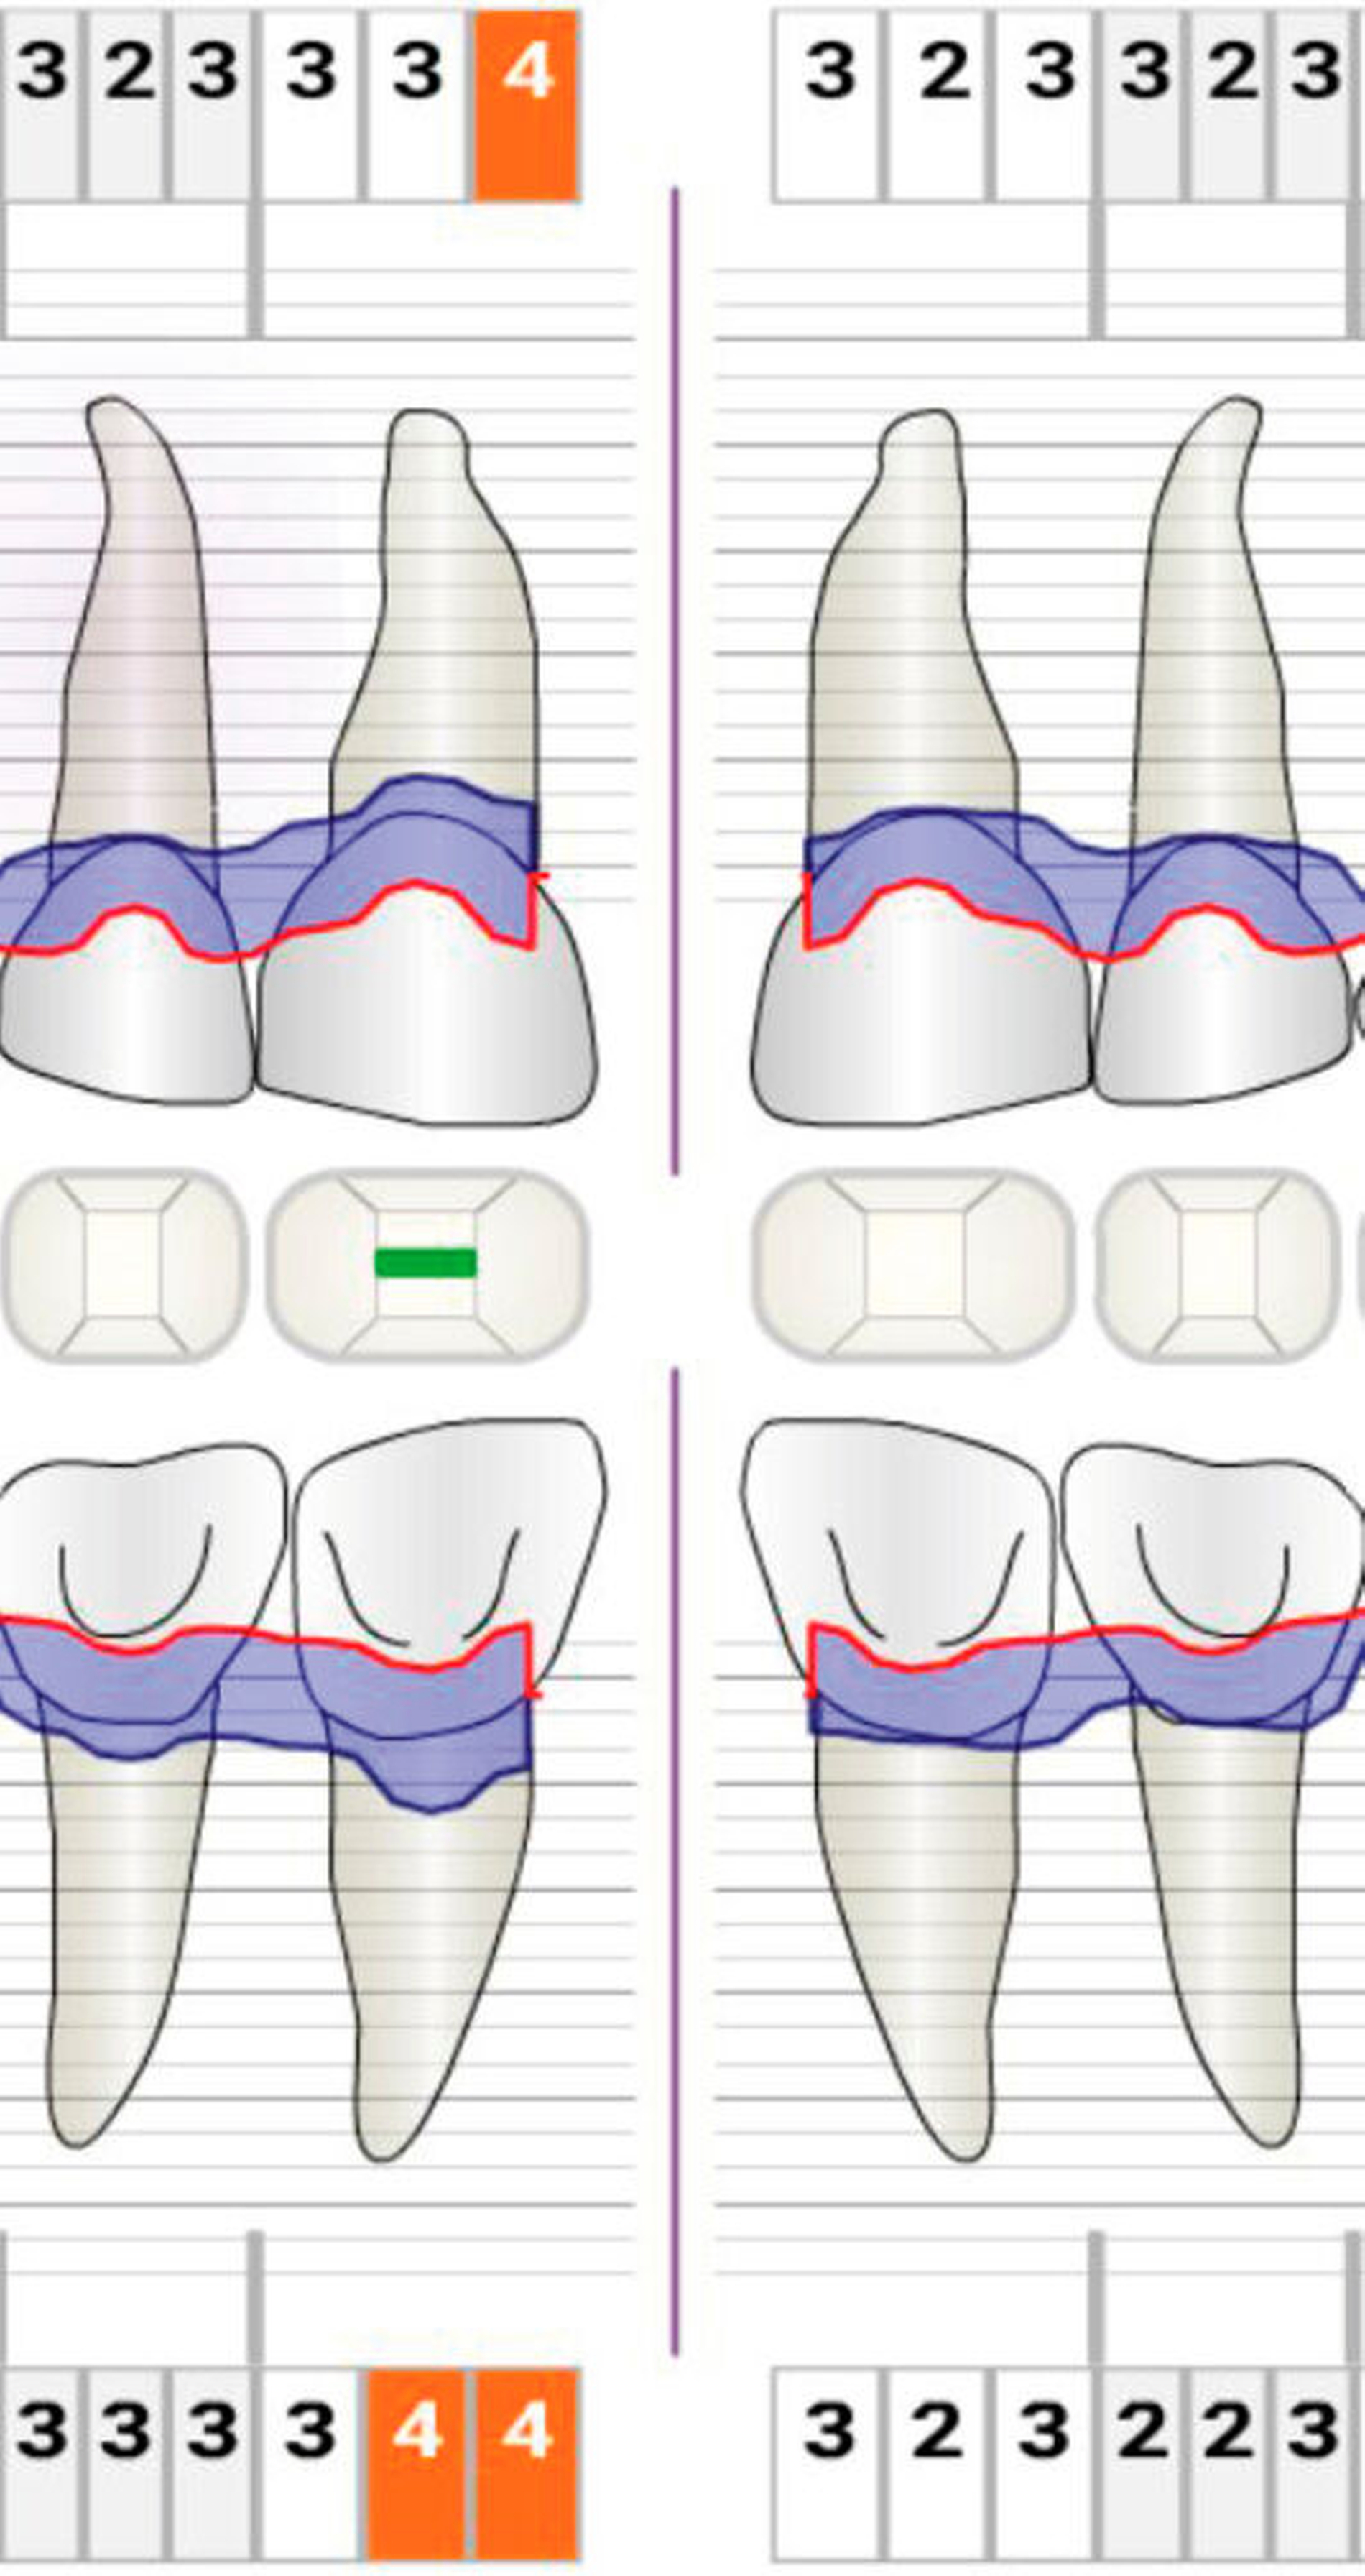

Die Anwendung mikrochirurgischer Prinzipien wurde im Zusammenhang mit unterschiedlichen parodontal-chirurgischen Eingriffen wissenschaftlich untersucht. Cortellini et al. behandelten 26 Patienten mit tiefen intra-ossären Defekten mittels geführter Geweberegeneration unter Anwendung eines Operationsmikroskops. Die Ergebnisse zeigten eine Zunahme des klinischen Attachmentlevels von im Mittel 82,8 ± 14,7 Prozent. Die Reduktion der Sondierungstiefen um 5,8 ± 1,4 mm ging mit einer minimalen Rezessionsbildung von 0,4 ± 0,7 mm einher. Die Autoren sahen die Vergrößerung des Operationsfelds und die bessere Beleuchtung als maßgeblich an, um die Gewebe präzise und atraumatisch zu behandeln. In 92,3 Prozent der Fälle kam es zu einer primären Wundheilung, die über den gesamten Wundheilungsprozess bestehen blieb [Cortellini & Tonetti, 2001].

In einer weiteren Studie der gleichen Gruppe wurden isolierte intraossäre Knochendefekte bei 13 Patienten mit einer minimalinvasiven chirurgischen Technik (MIST) und der Applikation von Schmelz-Matrix-Proteinen behandelt. Ein Operationsmikroskop sowie mikrochirurgische Instrumente und Nahtmaterialien wurden verwendet. Es kam zu keinen Ödemen oder Hämatomen. Die Patienten gaben keine Schmerzen an. Der klinische Attachmentlevel war nach einem Jahr um 88,7 ± 20,7 Prozent höher als zu Beginn der Behandlung. Eine primäre Wundheilung konnte in 92,3 Prozent erreicht werden [Cortellini & Tonetti, 2007]. Auch bei der Behandlung nebeneinanderliegender intraossärer Knochendefekte kam es unter den gleichen Bedingungen zu einer Zunahme des klinischen Attachmentlevels um 83 ± 20 Prozent. Die Patienten gaben moderate Schmerzen für den Zeitraum der ersten 21 ± 5 Stunden an. Eine primäre Wundheilung konnte in 100 Prozent der Fälle erreicht werden [Cortellini et al., 2008].

Cairo et al. untersuchten die Behandlung parodontaler Taschen mit flachen oder moderaten Knochendefekten (kleiner/gleich 3 mm) in der ästhetischen Zone unter Anwendung der „Fibre Retention“-Technik in Kombination mit Papillenerhaltungslappen. Die Heilung verlief in 100 Prozent der Fälle per primam und ohne besondere Vorkommnisse. Die Verwendung des Operationsmikroskops verbesserte die visuelle Wahrnehmung und erhellte das Operationsfeld, so dass die in der Tiefe der Defekte verbliebenen parodontalen Fasern besser identifiziert und erhalten werden konnten. Das Ergebnis zeigte eine Zunahme des klinischen Attachmentlevels, eine Reduktion der Sondierungstiefen und geringe Rezessionsausbildungen. Es gab keine postoperativen Komplikationen und die Patienten waren mit dem ästhetischen Ergebnis zufrieden [Cairo et al., 2008].